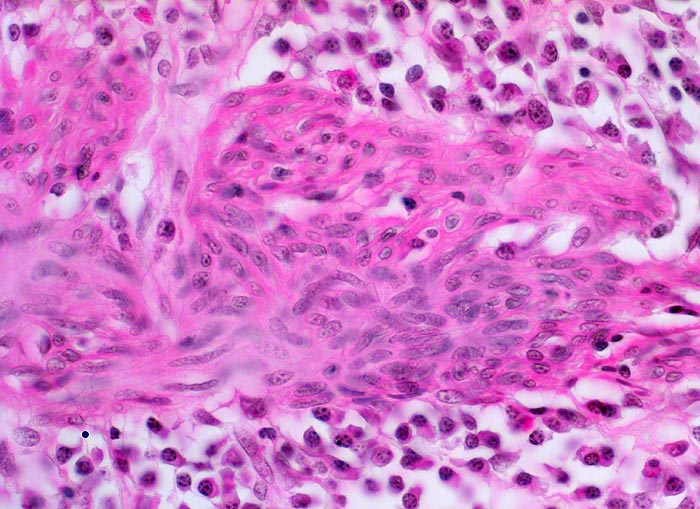

Die Colitis ulcerosa beginnt im Rektum (> 2758) und breitet sich kontinuierlich nach proximal aus. In 10% ist das gesamte Kolon (> 3364) befallen und es besteht zusätzlich eine back-wash-Ileitis im terminalen Ileum. Das Rektum ist bei unbehandelten Patienten praktisch immer befallen. Nach topischer Therapie kann das Rektum ausgespart sein und nach längerem Krankheistverlauf ist auch ein segmentaler Befall möglich. Bei fehlenden klinischen Angaben (Dauer der Erkrankung, Therapie) können diese atypischen Manifestationen diagnostische Schwierigkeiten verursachen. Makroskopisch finden sich häufig longitudinal ausgerichtete Ulzera mit Querverbindungen und Konfluenz. Residuelle Schleimhautinseln imponieren als Pseudopolypen. In der Remissionsphase ist die Schleimhaut glatt und blass, das Faltenrelief ist vergröbert und verstrichen und es finden sich häufig Granulationsgewebspolypen. Mikroskopisch findet sich je nach Entzündungsaktivität eine mehr oder weniger ausgeprägte diffuse Verdichtung des lymphoplasmazellulären Entzündungsinfiltrates mit Beimischung von Granulozyten in Form einer Kryptitis oder von Kryptenabszessen. Bei einer stark aktiven Entzündung finden sich zusätzlich Erosionen und Ulzera mit Ausdehnung der Entzündung über die Mukosa hinaus in die Submukosa oder in noch tiefere Schichten bei hochflorider Kolitis. Die Kryptenarchitektur ist gestört, die Anzahl der Krypten und der Becherzellen vermindert. In der Regeneratphase finden sich zahlenmässig reduzierte und verkürzte Krpyten mit normaler Anzahl Becherzellen. Meist bleibt eine leichte Verdichtung der Entzündungszellen in der Lamina propria bestehen.

Morphologische Merkmale:

• Abwechslungsweise oberflächliche Ulzera und pseudopolypöse Schleimhautvorwölbungen.

• Entzündungsinfiltrate in Mukosa und Submukosa.

• Unregelmässig geformte und verzweigte Krypten (Kryptenarchitekturstörung).

• Krpyten enden deutlich oberhalb der Lamina muscularis mucosae (Kryptenatrophie).

• Verminderte Schleimbildung und Becherzellverlust.

• Basal betonte Plasmozytose und Infiltrate neutrophiler Granulozyten.

• Ansammlungen neutrophiler Granulozyten in Kryptenlumina (=Kryptenabszesse) und Infiltrate von neutrophilen Granulozyten im Kryptenepithel (=Kryptitis).